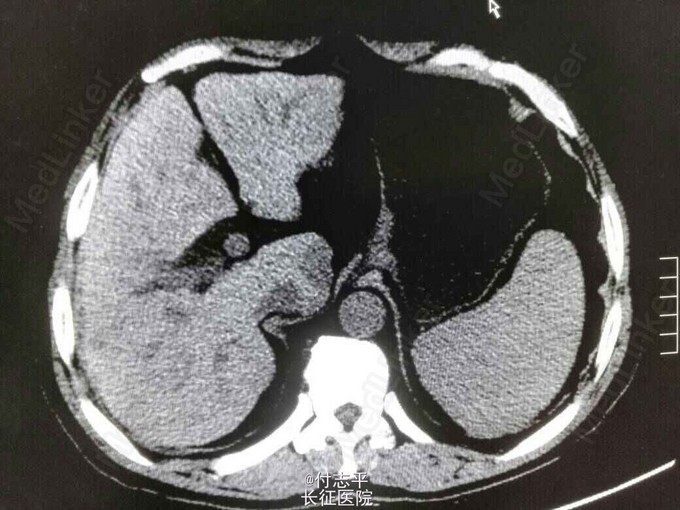

主诉:体检发现AFP升高2月,发现肝占位6天。 病史:患者63岁男性,2个半月前在当地体检发现AFP260.6ng/ml,门诊B超示肝硬化,因无任何伴随症状,未进一步检查。10天前复查 AFP570.3ng/ml,仍未行处理。遂来我院,门诊增强CT示肝尾装叶占位,肝硬化,脾大,脂肪肝,胆囊切除术后。患者一般情况尚可。3年前体检发现“乙肝病毒感染,肝硬化”,抗乙肝病毒治疗“恩替卡韦”至今。40年前因胆结石行胆囊切除术。长期饮酒史,服药后开始戒酒。无家族病史。

诊断:1.原发性肝癌。2.乙肝后肝硬化。3.胆囊切除术后。 治疗:完善术前检查后预备行肝尾状叶占位微波消融术。术中见小肠、大网膜、与原切口瘢痕和肝脏脏面广泛粘连,仔细分离暴露后见肝脏呈轻中度结节性肝硬化表现,质地较硬;于尾状叶实质内探及2cm质硬肿块,边界不清,周围组织及器官未见明显侵犯。由于肿瘤位置较深,超声探头不好摆放,改行肝尾状叶切除术。

随访:术后恢复情况可,无明显并发症。病理回报肝细胞性肝癌,中分化;包膜侵犯(-),手术切缘 (-),卫星灶 (-),脉管癌栓(+)。 讨论:患者术前检查后拟行术中微波消融术,可是由于多年前的手术治疗造成组织大量粘连,造成了器械操作的困难,遂改行手术完全切除肿瘤。由于肿瘤位置较深,加上肝硬化,较难止血,出血约800ml,风险很大。